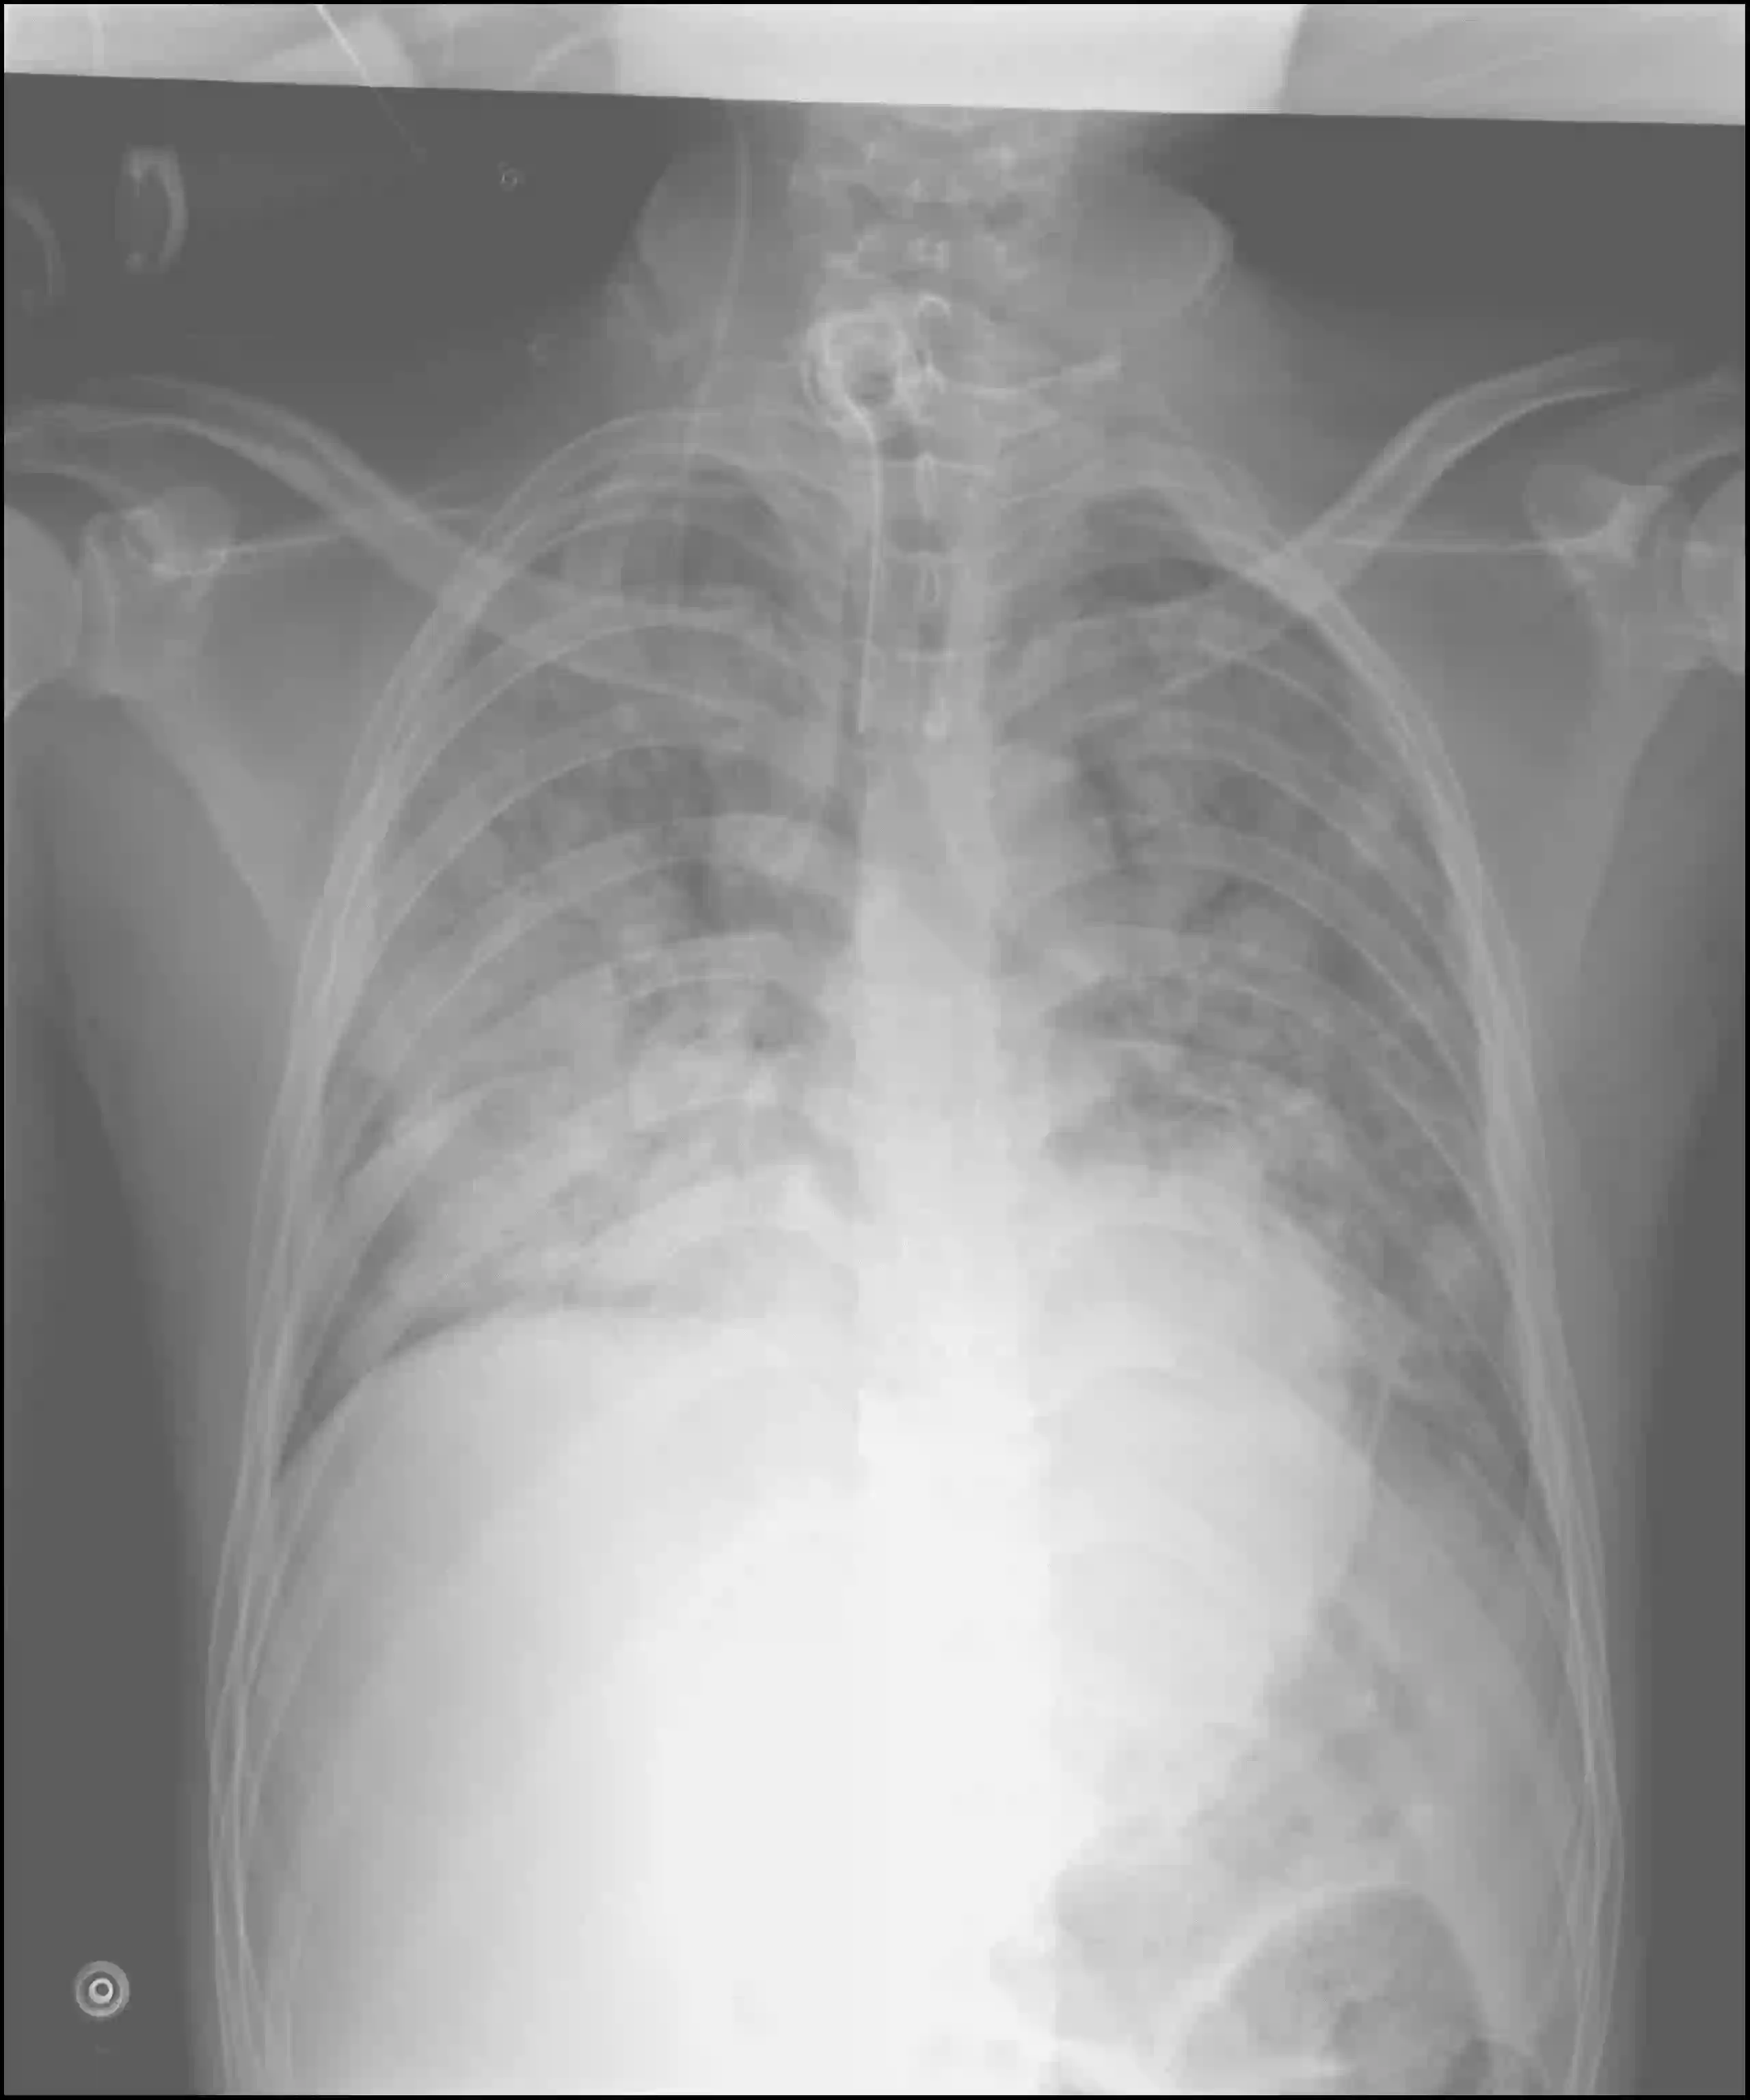

Vietnamese medical research has become an increasingly vital domain, particularly with the rise of intelligent technologies aimed at reducing time and resource burdens in clinical diagnosis. Recent advances in vision-language models (VLMs), such as Gemini and GPT-4V, have sparked a growing interest in applying AI to healthcare. However, most existing VLMs lack exposure to Vietnamese medical data, limiting their ability to generate accurate and contextually appropriate diagnostic outputs for Vietnamese patients. To address this challenge, we introduce ViX-Ray, a novel dataset comprising 5,400 Vietnamese chest X-ray images annotated with expert-written findings and impressions from physicians at a major Vietnamese hospital. We analyze linguistic patterns within the dataset, including the frequency of mentioned body parts and diagnoses, to identify domain-specific linguistic characteristics of Vietnamese radiology reports. Furthermore, we fine-tune five state-of-the-art open-source VLMs on ViX-Ray and compare their performance to leading proprietary models, GPT-4V and Gemini. Our results show that while several models generate outputs partially aligned with clinical ground truths, they often suffer from low precision and excessive hallucination, especially in impression generation. These findings not only demonstrate the complexity and challenge of our dataset but also establish ViX-Ray as a valuable benchmark for evaluating and advancing vision-language models in the Vietnamese clinical domain.